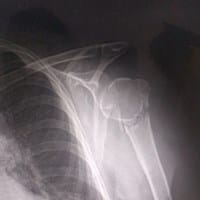

¿Rayos x, el humero está roto?

El hueso humero del brazo derecho está safado (dislocado), pero quisiera saber si la diafisis está rota, justo abajo de la epífisis. Fue a causa de una caída, en caso de las radiografías, quisiera saber como es que se debería proceder con la...

Sin respuestas